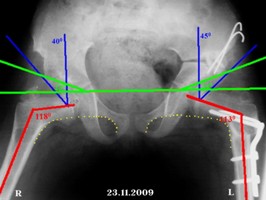

Рентгенограмма после открытого вправления вывиха правого бедра, корригирующей остеотомии обеих бедер и остеотомии таза с двух сторон по Солтеру (справа металлические конструкции удалены). Головки обеих бедер центрированы в вертлужной впадине, анатоми-ческие соотношения элементов тазобедренного сустава восстановлены (рис. 2).

Рис. 2. Рентгенограмма таза. Переднезадняя проекция. Состояния после оперативного лечения. Красными линиями указаны шеечно-диафизарные углы после операции (правый – 1180 и левый –1130). Синими – углы Виберга (правый – 400 и левый – 450). Зеленым – указаны ацетабулярные углы (правый – 230 и левый – 240).